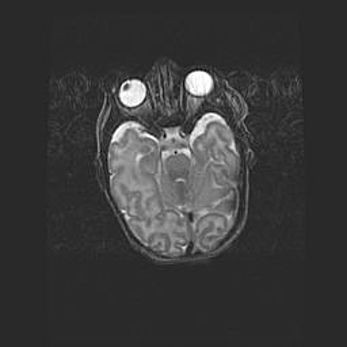

Множественные кисты обоих полушарий головного мозга, наибольшая из них в правой затылочной области. Ассиметричная атрофическая гидроцефалия.

Возраст: 7 месяцев

Вес: 5660 г

Пол: мужской

Окружность головы: 41,5 см

Срок гестации: 28-29 недель

Кисты головного мозга развиваются в результате многоочаговых некрозов вещества мозга и возникают вследствие перенесенной перинатальной инфекции, менингитов, энцефалитов, асфиксии, родовой травмы, расстройств мозгового кровообращения различного генеза. Образованию кист в веществе головного мозга плодов и новорожденных способствуют такие факторы, как высокое содержание в нем воды, недостаточная (или отсутствие) миелинизация и слабая астроглиальная реакция на повреждение.

Кисты могут сочетаться с гидроцефалией и другими поражениями головного мозга.